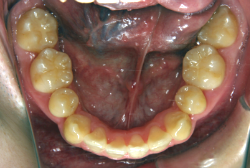

叢生(そうせい)

凸凹な歯並びのことを叢生といいます。矯正歯科に来院する患者様の主訴の中で、最も多いのが「配列の凸凹を真っ直ぐにしたい」というものです。歯の大きさと顎の大きさの調和がとれていないことが原因です。

凸凹を主体としたケースの場合、当院の平均治療期間は18ヶ月ですので、このケースは少し長めに経過しました。理由の一つは凸凹の程度がかなり重症だったと言うことですが、もう一つは、右下第2大臼歯が45度くらい前傾していたため、それを整直化させるために時間を要したと考えています。いずれにしても最終結果は大変よい状態と思います。

治療前は並びが乱れて見た目が悪いというのはもちろん問題ですが、歯科医学的に一番困るのは噛み合わせが悪いという点です。上下の犬歯(3番目の歯)は、上下的に離れた位置にあるため接触することができません。つまり歯としては存在していても、歯としては機能していないということです。